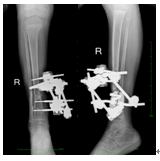

术后: